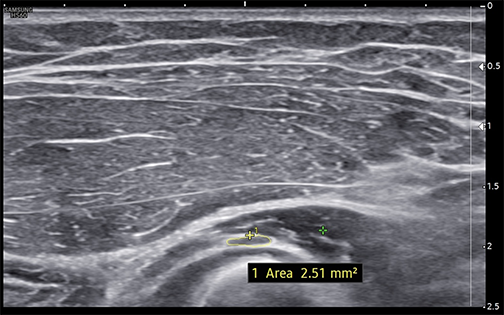

Measured short-axis ultrasound image of the deep motor branch of the radial nerve, a few millimeters distal to the arcade of Frohse, showing a cross-sectional area of 2.51 mm² (normal <3.0 mm²).